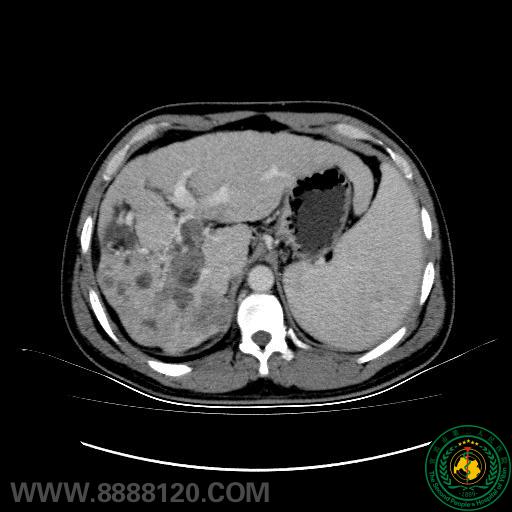

以前,肝癌合并门静脉癌栓为肝癌经肝动脉化疗栓塞术(TACE)的相对禁忌症,患者生存期短,即便采用姑息性化疗栓塞术,术后也可能因肝功能衰竭、门静脉高压加重而导致上消化道出血,且癌栓进行性扩散会形成恶性循环,使得患者肝功能显著下降。近期,我院影像科介入室对此类患者的治疗取得了突破。具体方案为:先行门静脉支架植入开通门静脉通路,再行肝动脉化疗栓塞术。

我们通过对几例行肝动脉化疗栓塞联合门静脉支架置入术患者随访,发现肿瘤原发病灶及癌栓控制均良好,提示该法具有以下优点:1、恢复门静脉血流动力学,减少门脉高压性消化道出血机率;2、促进正常肝叶过度灌注、代偿性肥大,纠正或改善肝功,为二期外科手术提供条件;3、控制癌栓门静脉的进一步侵袭、蔓延,利于TACE治疗效果。